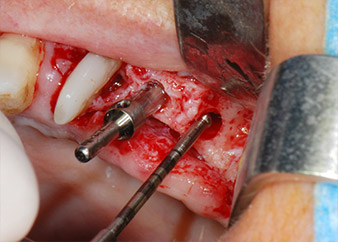

Nous avons toutefois maintenu notre projet initial de conservation des deux dents comme piliers temporaires d'un bridge pendant la période de six mois nécessaire à l'ostéointégration des implants. À la prochaine incision, la situation devrait être réétudiée. Premièrement, afin de gérer le problème endoparodontal, la surface de racine restante a été soigneusement débridée à l'aide d'un équipement piézoélectrique (Piezomed, W&H, utilisé avec l'insert en forme de spatule S1, initialement conçu pour limer la paroi sinusienne latérale) (Fig. 4).

Puis l'apex a été limé à l'aide du même instrument afin d'éliminer les tissus apicaux infectés résiduels et de réduire les éventuelles ramifications des canaux radiculaires (apicectomie) (Fig. 5). Il n'a pas été nécessaire de procéder à une obturation rétrograde car l'obturation orthograde venait juste d'être reprise.